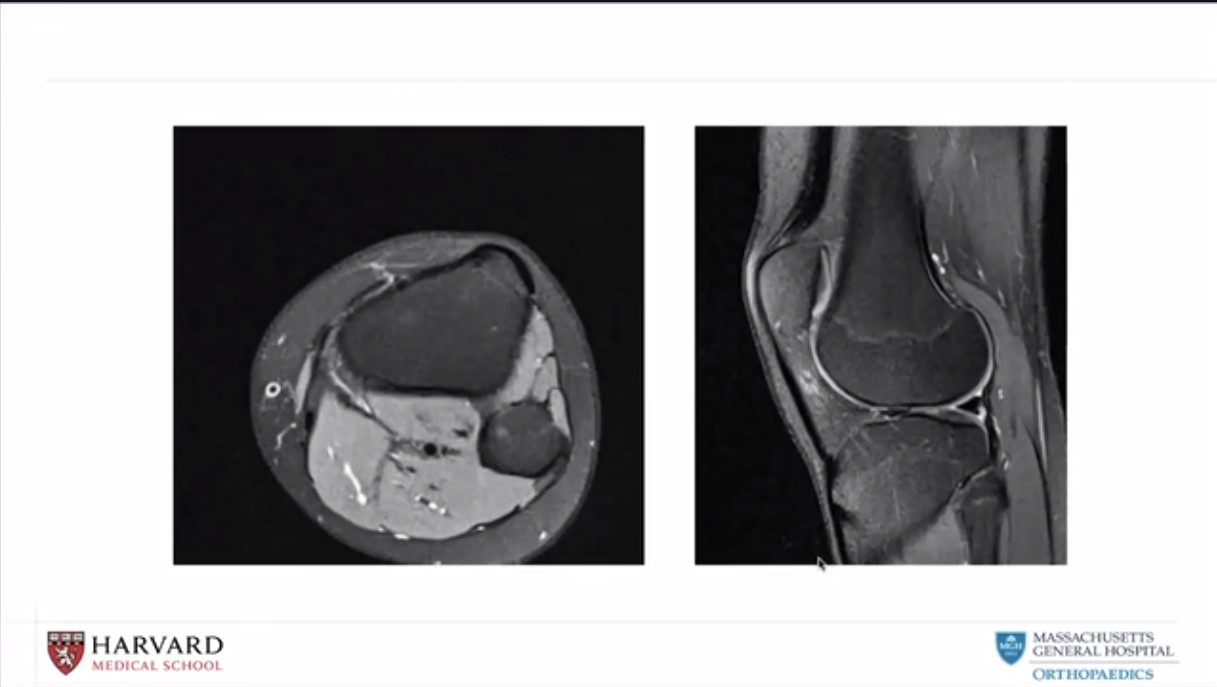

#004: Florian Dirisamer - Meniskus-Allograft-Transplantation

My Experience - Why MAT?